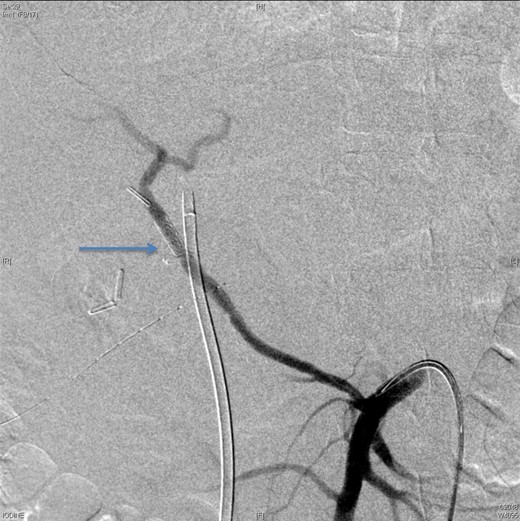

Upon presentation to our center, the patient was febrile (38.9°C) and complained of a left upper limb pain and swelling. The surgical drain was draining a mixture of bile and blood. His WBC count was 14 × 109/l, total bilirubin 35 µmol/l and the direct bilirubin 21 µmol/l. A duplex ultrasound of the upper limb revealed a left brachial vein thrombosis. Hematology was consulted, and a diagnosis of acute upper limb venous thrombosis was established. Owing to the presence of blood in the drain, he was kept on the maximum prophylactic dose of unfractionated heparin. A CT angiography of the abdomen showed two collections, one at the surgical bed near the drain, and the other was subcapsular below the left lateral lobe of the liver, as well as an aneurysm of the replaced right hepatic artery with an active bleeding blush (Fig. 1). The patient was immediately referred for an angiography, which confirmed the CT scan findings (Fig. 2). An arterial stent was inserted at the location of the aneurysm (Fig. 3), and a pigtail drain was inserted to drain any residual collection. An ERCP was also performed, which revealed a Strasberg Class D injury, and a plastic biliary stent was inserted. After the angio-stent insertion and stabilization of the patient, heparin infusion was started. Five days later he developed hematemesis and melena with a significant drop in his Hb to 2 g/l, and his total bilirubin became 183 μmol/l of which 91 μmol/l is direct. A gastroscopy was performed and showed hemobilia (bleeding from the ampulla of Vater). Subsequent angiography demonstrated a leak of contrast just above the arterial stent; hence, a further stent was placed to cover that area of the aneurysm. Similar symptoms reoccurred a week later, and a new angiography showed a new aneurysm from the left proper hepatic artery. A percutaneous thrombin injection of the aneurysm was performed as the bleeding branch was unreached via direct angiography and was filling in retrograde perfusion. During recovery a chest spiral CT was performed, which revealed the diagnosis of a bilateral segmental pulmonary embolism. Heparin infusion with low targets of partial thromboplastin time of 50–60 was started.

A CT scan showed replaced right HAP inside the collection (straight arrow).